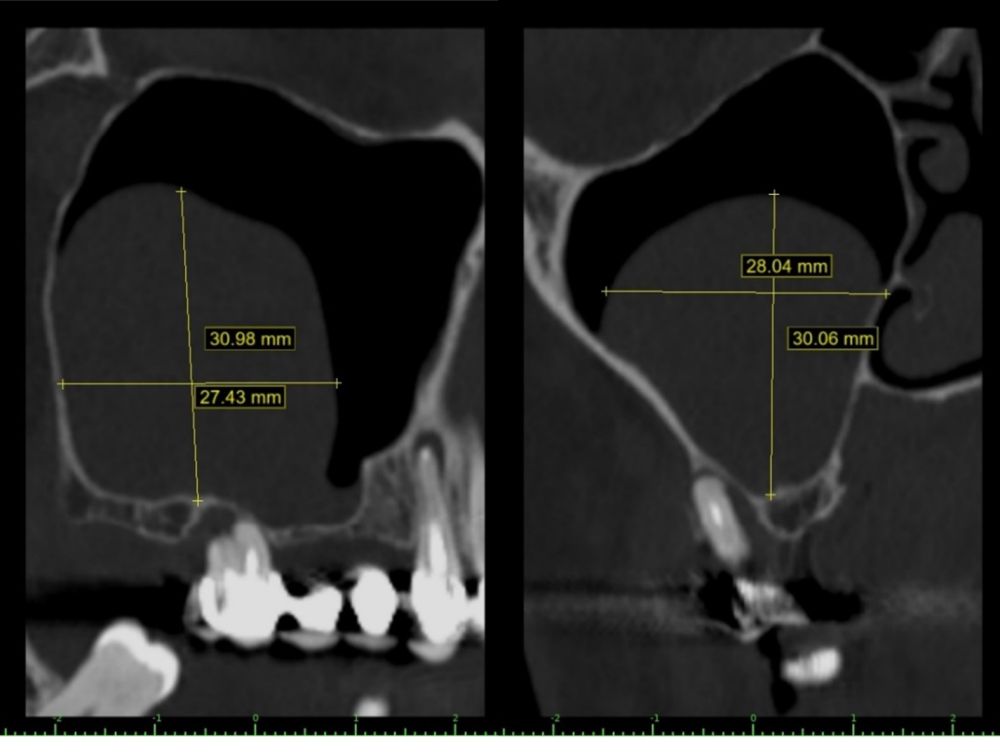

En la exploración radiográfica mediante escáner se apreció una lesión apical de pequeño tamaño en el 1.4 y una escasa disponibilidad ósea. Además, se observó imagen radioopaca cupuliforme de 3 x 2,8 cm en el seno maxilar derecho, compatible con un pseudoquiste sinusal (Figura 2). La extensión craneal alcanzaba la mitad superior del seno maxilar y el volumen de la lesión (5 cm³) era aproximadamente ⅓ del volumen sinusal (Figuras 3 y 4).